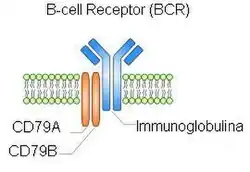

Various new drugs such as B-cell receptor (see adjacent figure) signaling blockers and ibritumomab tiuxetan (Zevlin) are being tested in clinical trials for MZL.[79] These trials are important in determining dosages and safety of the drugs in study. As of January 19, 2017, the FDA approved the first ever targeted drug for MZL, ibrutinib.[80] This drug works by inhibiting Bruton's tyrosine kinase (BKT), which is able to send signals to the nucleus for survival. In other words, it slows the growth of B-cells.[80] Vaccines have been developed that greatly reduce the number of Helicobacter pylori in the stomach of animals previously colonized with these bacteria. One or more of these vaccines may be a promising candidates to control Helicobacter pylori infection in humans as well as farm and domesticated animals.[81]